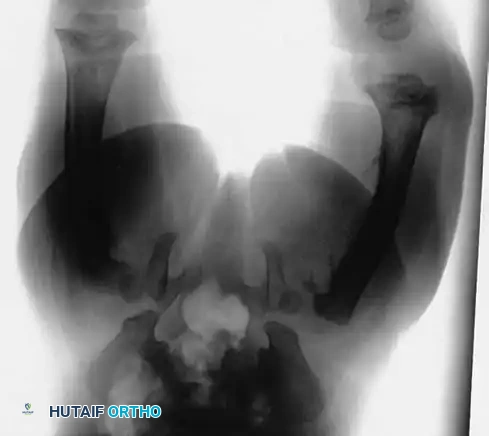

To rule out or confirm this possibility, a comprehensive skeletal survey (and often a bone scan) is strictly indicated.

Image

Pathognomonic Radiographic Findings:

1. Multiple Fractures in Different Stages of Healing: The presence of acute fractures alongside fractures exhibiting mature callus formation almost always indicates repeated episodes of non-accidental trauma.

2. Epiphyseal-Metaphyseal ("Corner" or "Bucket-Handle") Fractures: These are highly specific to child abuse. They result from violent pulling, twisting, and shearing forces applied to the infant's limbs, which are rarely replicated in accidental trauma.